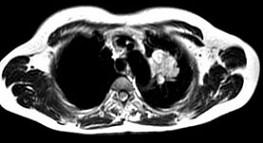

问题 男,68岁,声音嘶哑半月,行MRI检查如图,其最可能的诊断为 ( )

选项 A、左上肺癌 B、左上肺动静脉瘤 C、左上肺结核球 D、左上肺炎性假瘤 E、右上肺癌

答案 A